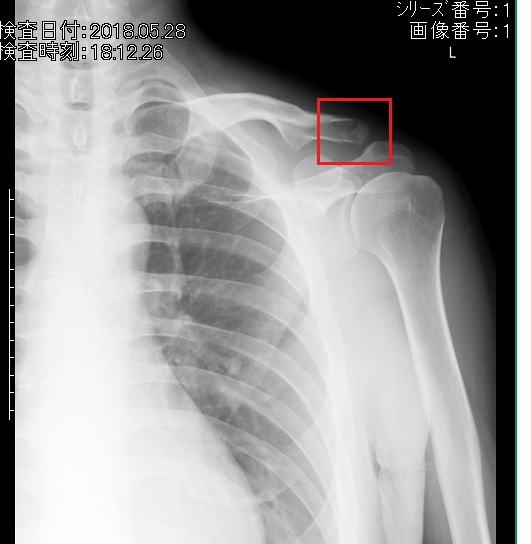

原因は5月末にした鎖骨骨折。「ひび」のレベルでズレてもいないので軽傷なのですが、なにせ肩が思うように動かせないのは不便。